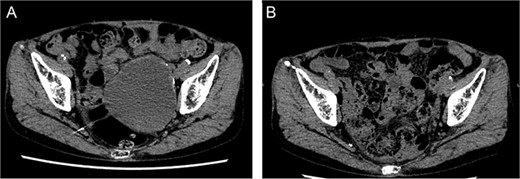

She underwent surgery under general anesthesia. A midline abdominal incision and an intraperitoneal approach were employed. The retroperitoneal space was accessed from the lateral side of the sigmoid colon to reach the CIA. The aneurysm was incised midway. The hematoma and coils were removed, and the stent graft was observed. The laparoscope was utilized to inspect areas obscured from direct view, such as behind the stent graft, to confirm that no type I or IIIb endoleak was present (Fig. 5). A type II endoleak was observed near the proximal neck of the stent graft, which was thought to be the cause of the aneurysm expansion. The IIAA was sutured with 3–0 monofilament, and the aneurysm was closed. The left ureter was close, and care was taken during suturing to avoid including it in the stitches. The operation took 177 min, and the patient was discharged on the tenth day postoperation. Follow-up CT at 7 months postoperation showed a reduction in aneurysm size (Fig. 6).

Laparoscopic view of checking for type I endoleak presence. SG, stent graft.

Postoperative computed tomography showing a reduction in aneurysm size. A—Preoperative image, B—7-month postoperative image.